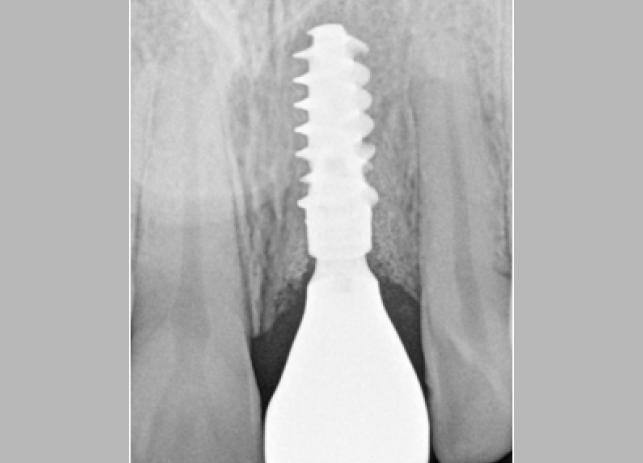

Этот пациент обратился ко мне с жалобами на сильную боль, покраснение и отек вокруг только что установленной коронки на имплантате. В анамнезе было следующее: был снят аналоговый оттиск с уровня имплантата и отправлен в лабораторию для изготовления коронки. У лаборанта не было указаний относительно расположения шейки имплантата по отношению к мягким тканям и кости.

Была выбрана самая короткая высота десневой манжеты (GH), так как она является наиболее безопасной с эстетической точки зрения, поскольку металлическая кромка не будет видна над десной. При доставке коронки на имплантат стоматолог столкнулся с трудностями при «посадке» коронки на абатмент.

Коронка была установлена со значительным сопротивлением для достижения необходимого значения торка. Ущемление твердых и мягких тканей из-за очень острого профиля выступа вызывает давление на кость, что приводит к некрозу и, в конечном итоге, к потере маргинальной кости в этой области. Чтобы избежать подобных осложнений, необходимо выбирать правильный абатмент.

На основе ОПТГ, сделанного после установки или имплантата (рис. 2), стоматолог может выбрать подходящую высоту десневой манжеты для абатмента и направить техника, предоставив рентгеновский снимок и/или спецификацию формирователя десны. Большинство систем имплантатов имеют синхронизированные формы и контуры хирургических абатментов и компонентов протеза.